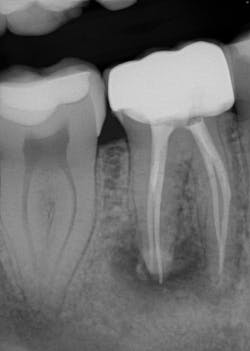

Various clinical presentations and risk factors can influence endodontic success or failure, including but not limited to the quality of the root canal performed and the seal of the coronal restoration.2 In addition to the aforementioned factors, the presence and size of a periapical lesion can directly affect the prognosis and treatment outcome. Classic literature highlights this shift in long-term success rates from 96% for vital/nonvital cases without the presence of a periapical lesion to 86% when a periapical lesion is present.3

Periapical radiographs have been commonly used to evaluate the size of periapical lesions. However, periapical radiographs have limitations, because the information is rendered in only two dimensions. A periapical lesion can only be detected in the radiograph when the mineral loss of bone reaches 30%–50%.4